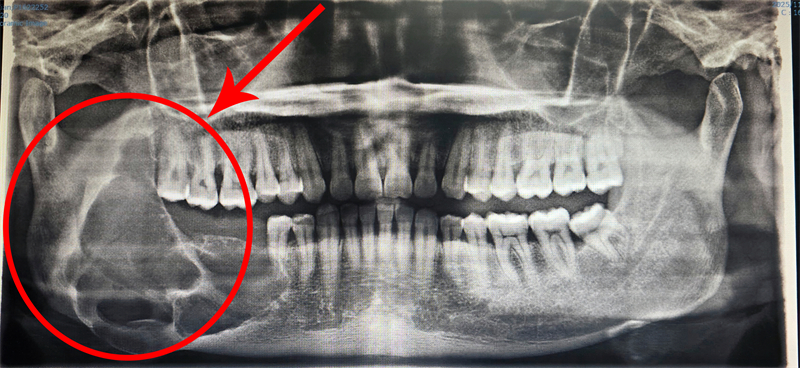

口腔頜面外科陳裕聰副主任醫師接診后,第一時間感受到患者的焦慮與無助,當即安排全面影像學檢查。檢查結果顯示,成釉細胞瘤已然復發,病變范圍大幅擴大,右下頜骨升支遭嚴重破壞,若拖延治療,不僅會導致面部畸形,更會造成不可逆的功能障礙。

深知患者的迫切需求,手術團隊反復研讀影像報告,結合患者身體狀況反復推演,最終量身定制“數字化手術導板+腓骨移植”的個性化治療方案。

一邊,醫生借助數字化定制手術導板,鎖定病變組織,在保留健康組織、減少創傷的前提下,清除腫瘤病灶;另一邊,另一組醫生在患者小腿截取適配長度的腓骨,經塑形后,與頜骨缺損處契合。